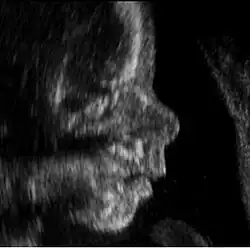

Der Physiologe Davenport Hooker untersuchte in den 30er Jahren des zwanzigsten Jahrhunderts Reflexe bzw. Reaktionen von abgetriebenen Föten extrauterin.[4] Die motorischen Fertigkeiten von Embryo und Fötus lassen sich mittlerweile mit Hilfe der Ultraschalltechnik vergleichsweise gut empirisch untersuchen. Ab der 8. Woche bewegt der Embryo bereits den Rumpf, kurz danach zeigen sich Bewegungen der Extremitäten.[5] Mit Hilfe der Ultraschalltechnik ließ sich nachweisen, dass es sich hierbei nicht nur um Reflexe handelt, sondern auch um endogen ausgelöste Bewegungen.[6] Nach Auffassung von Alessandra Piontelli zeigt der Fötus alle Bewegungsmuster, die später dann auch beim neugeborenen Baby gefunden werden.

Die italienische Neuropsychiaterin Alessandra Piontelli (* 1945) legte 1992 eine empirische Studie zum Verhalten reifer Föten vor, in der sie Ergebnisse ihrer Untersuchungen von elf Föten mit Hilfe der Ultraschall-Technik (Sonographie) darstellte.[50] Auch in späteren Anschlussuntersuchungen von Zwillingsschwangerschaften zeigte sich ein komplexes Verhaltensrepertoire der Föten, die sich untereinander stark durch ihre Formen der Aktivität unterschieden.[51] Sie reagieren auf Reize in komplexer Weise. Piontellis Studie legte nahe, dass bestimmte pränatale Erlebnisse das postnatale Leben stark bestimmen. Psychische Merkmale wie etwa verstärkte orale Aktivität sind vorgeburtlich erkennbar und zeigen sich auch nachgeburtlich. Nachuntersuchungen im Kleinkindalter wurden von ihr auf psychoanalytische Weise interpretiert. Es zeigte sich eine weitgehende Kontinuität von prä- und postnataler Entwicklung. Die Studie von Piontelli ist insofern bemerkenswert, als sie zum einen empirische Daten erhebt und zum anderen Einzelfälle prä- und postnatal im Sinne einer Längsschnittstudie untersucht. Die Untersuchung zeigt also eine Kombination sowohl des Wissenschaftsverständnisses der akademischen Psychologie als auch der Hermeneutik der psychoanalytischen Schulen. Das macht diese Studie ausgesprochen illustrativ und einzigartig in der wissenschaftlichen Landschaft.